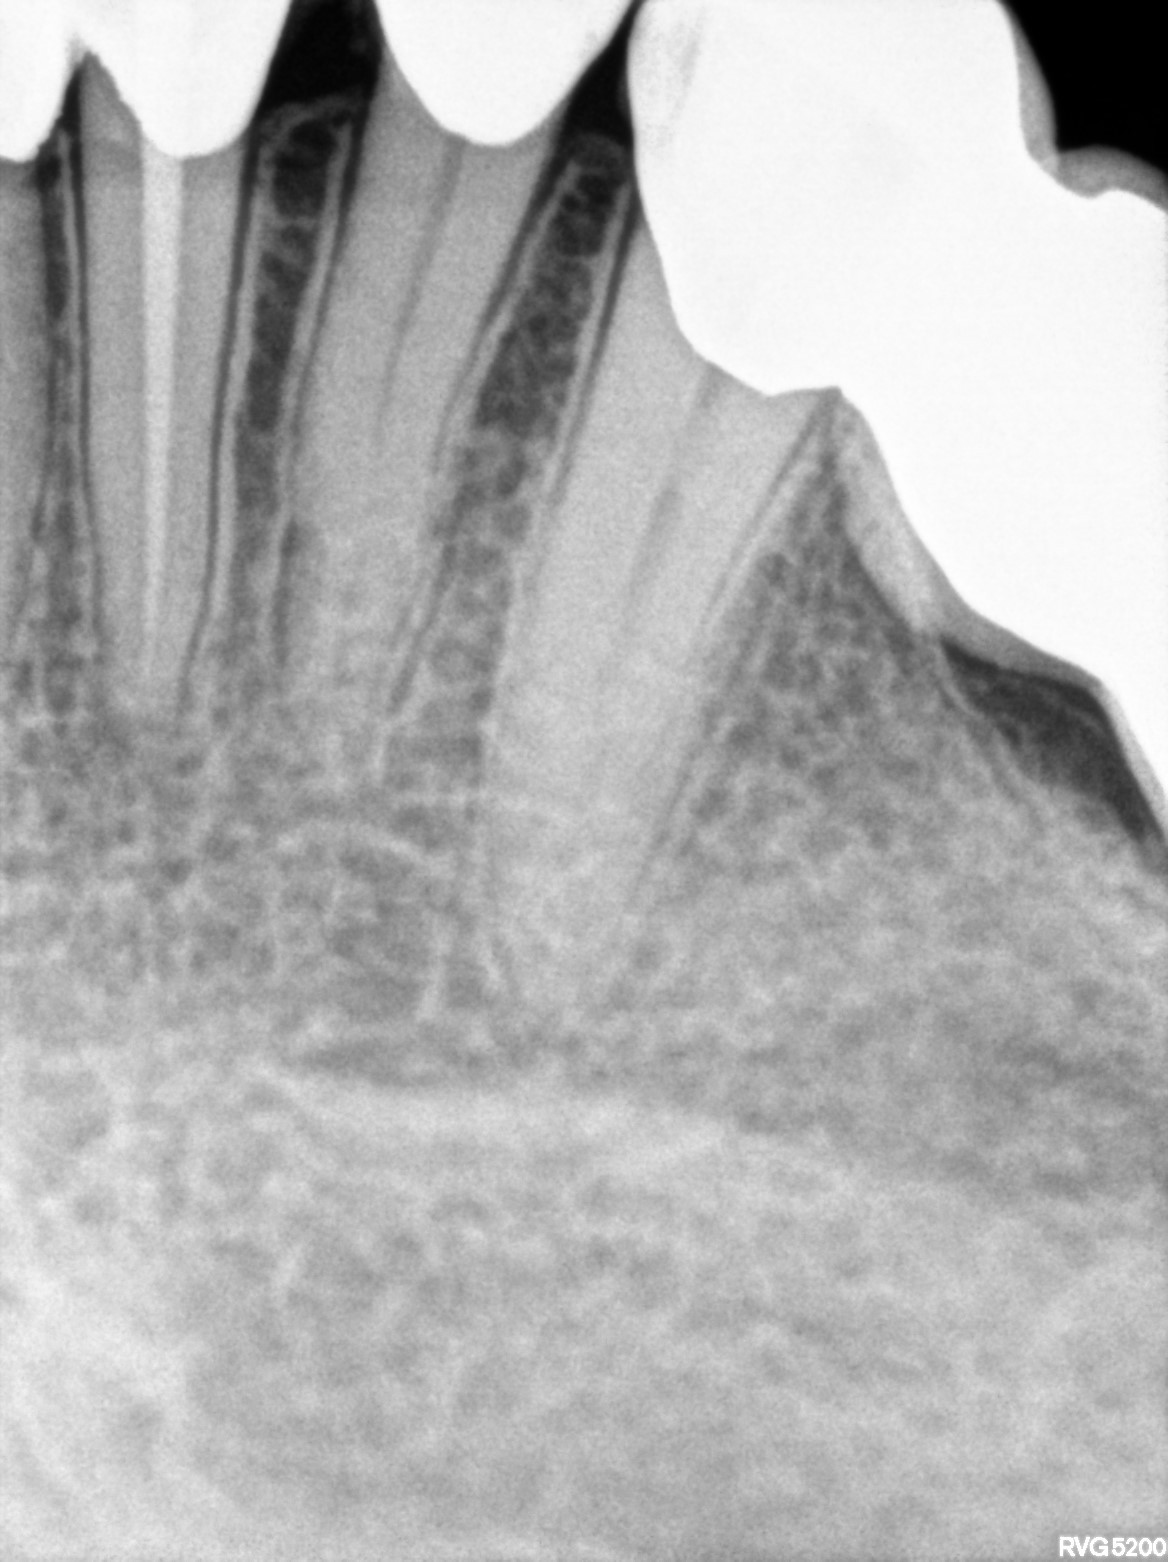

Dental Radiographs FHIR: DocumentReference · LOINC 24641-7

xray_1765005927_0.jpg

24641-7